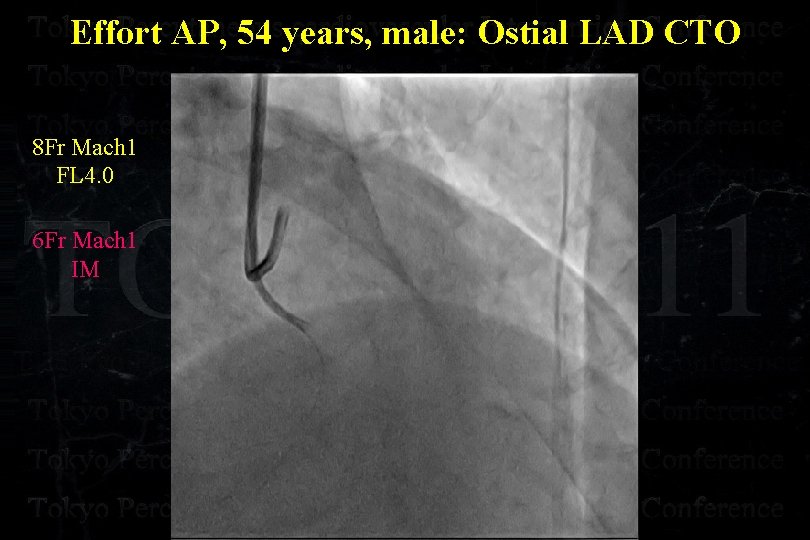

Effort AP, 54 years, male: Ostial LAD CTO

Effort AP, 54 years, male: Ostial LAD CTO

Effort AP, 54 years, male: Ostial LAD CTO

Effort AP, 54 years, male: Ostial LAD CTO

Effort AP, 54 years, male: Ostial LAD CTO

Effort AP, 54 years, male: Ostial LAD CTO

Effort AP, 54 years, male: Ostial LAD CTO Separated Conus Branch !

Effort AP, 54 years, male: Ostial LAD CTO 8 Fr Mach 1 FL 4. 0 6 Fr Mach 1 IM